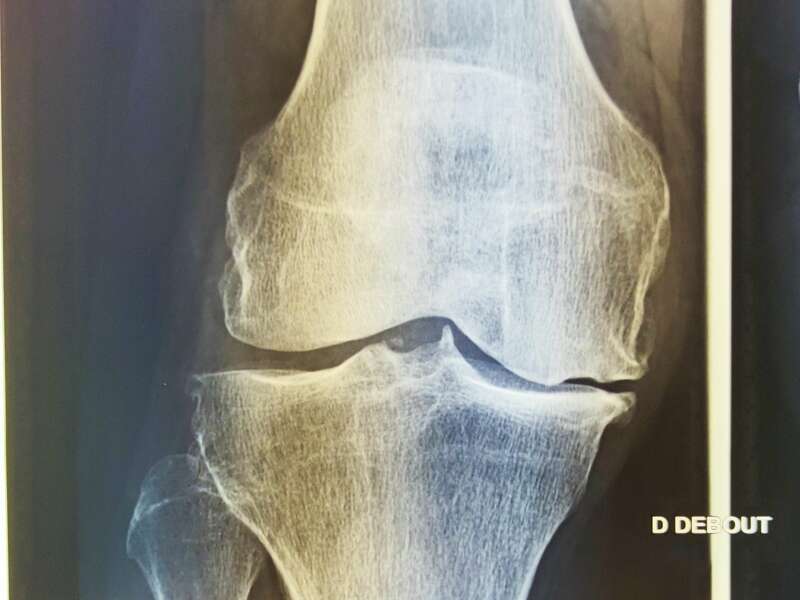

Comment faire le diagnostic d'arthrose?

Le diagnostic d’arthrose repose sur l’interrogatoire et l’examen clinique. Le médecin interrogera le patient pour déterminer la nature des symptômes et leur évolution, recherchera d’éventuels facteurs de risque, et étudiera le retentissement sur la vie quotidienne.

L’examen clinique évaluera la mobilité articulaire et recherchera un diagnostic différentiel : douleurs projetées sur le genou d’une pathologie rachidienne ou de la hanche, tendinite, lésions ménisco-ligamentaire.

Elle sera confirmée par des examens radiologiques tels que des radiographies du genou. En cas de doute diagnostic ou afin de rechercher d’éventuelles lésions associées, un scanner et/ou une IRM pourront être prescrits.